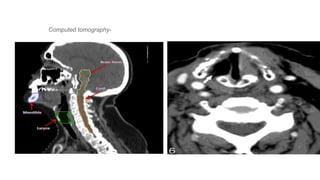

Computed tomography-

• 31.

• 32.